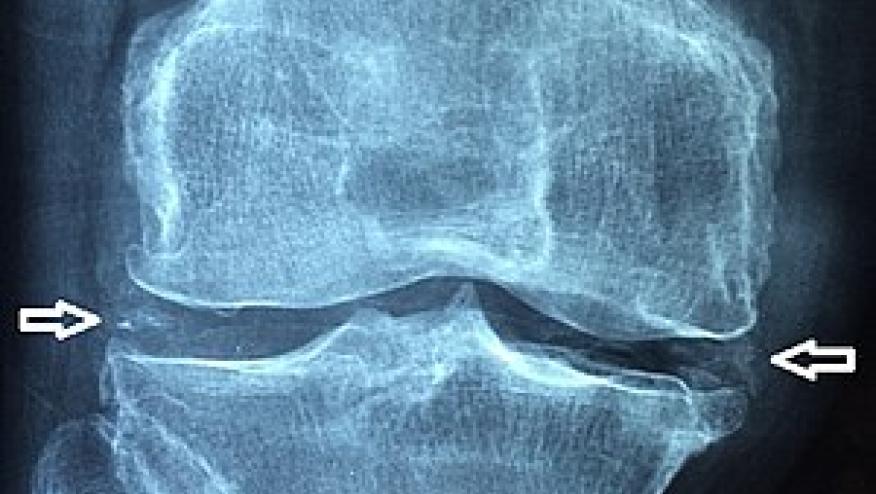

Analysis of data from two large, prospective cohort studies show that knee chondrocalcinosis was associated with an increased risk of incident knee osteoarthritis.

Chondrocalcinosis is not thought to be a requisite feature of OA, but is often found to associate with osteoarthritis development. Chondrocalcinosis and the presence of calcium pyrophosphate crystals in cartilage, may accelerate cartilage breakdown and joint damage. This study specifically examined whether if chondrocalcinosis before radiographic osteoarthritis may further contribute to the development of OA.

Chondrocalcinosis was found in 5% of osteoarthritis-free participants at baseline. It was significantly associated with incident knee osteoarthritis in both cohorts (pooled odds ratio [OR]: 1.75, 95% CI: 1.35-2.27, P < .001), with significance maintained in KLG = 0 participants (pooled OR: 1.77, 95% CI: 1.04-3.01, P = .035).